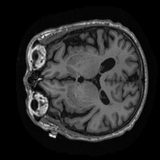

Sample MRI Scans

9 samples

Animated sagittal slices from ADNI-1 subjects across diagnostic groups

CN

CN Subject 2

Animated GIFs show 20 sagittal slices near the brain midline.